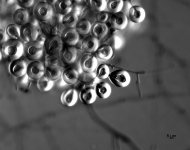

| Species Name: | Aspergillus spinulosporus |

| Taxonomy: | FUNGI Ascomycota, Eurotiomycetes, Eurotiales, Aspergillaceae |

| Characters: | CULTURE CONDITIONS heavy ascomata on PDA - // HUMAN/ ANIMAL PATHOGEN cerebral aspergillosis in a small bowel transplant patient - // MOLECULAR SYSTEMATICS calmodulin sequence has 99% identity to 5 strains of E. echinulata in the GenBank - fide P. Iwen (Click for publications citing UAMH 10948) |